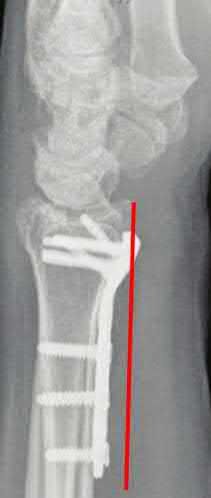

A 45-year-old manual laborer presents with chronic radial-sided wrist pain, recalling a fall on an outstretched hand 5 years ago. Imaging shows a scaphoid nonunion with radioscaphoid and capitolunate arthritis, but the radiolunate joint remains completely preserved.

This describes which stage of Scaphoid Nonunion Advanced Collapse (SNAC), and what is a standard surgical option?

Explanation

The progression of SNAC wrist is predictable. Stage 1 involves arthritis at the radial styloid; Stage 2 involves the entire radioscaphoid joint; Stage 3 involves the capitolunate joint; Stage 4 involves the radiolunate and/or entire carpus. Because the radiolunate joint is preserved in Stage 3, a four-corner fusion (capitate, hamate, lunate, triquetrum) with scaphoid excision is the standard salvage procedure. Proximal row carpectomy is contraindicated due to capitolunate arthritis.